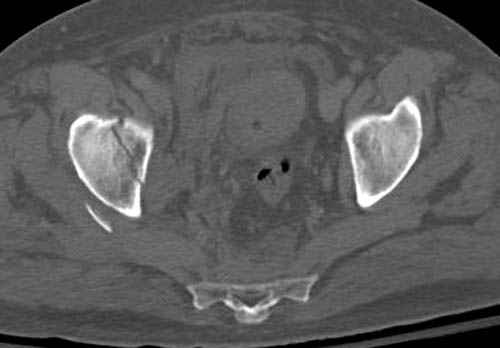

Наш недавний случай перкутанной фиксации "методом

Сиэтла" спицами 2.8 мм с резьбой на конце.

Прооперирован вчера на 13 день после поступления.

Больному 41 и из-за гемодинамической нестабильности в течение первых 7 дней был в реанимации под интубационной седацией.

Кроме перелома плеча у больного старый дистракционный перелом T12-L1 оперированный когда-то и кем-то, открытый перелом костей предплечья, который был прооперирован в ночь поступления, после I&D (хирургической обработки). Из-за разрыва селезенки при поступлении травма хирургами произведено удаление.

Дополнительно имеется перелом ацетабулума: задняя

колонна с полупоперечным переломом, и переломы костей лица.

На седьмой день зафиксирован перелом ацетабулума через задний доступ. Перед операцией для профилактики DVT, IVC фильтер, также получает Lovenox.

Извиняюсь за качества снимков, обычный больной в 300 фунтов, портативным ренген аппаратом не пробить.